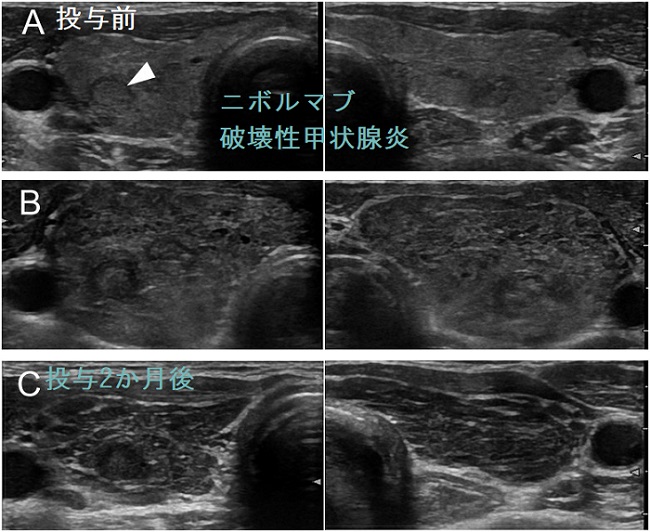

ニボルマブ(オプジーボ®)破壊性甲状腺炎の経過[J Endocr Soc. 2018 Feb 6;2(3):241-251.]

ニボルマブによる無痛性甲状腺炎(破壊性甲状腺炎)は、通常の無痛性甲状腺炎(破壊性甲状腺炎)と異なり、沈静化した後に永続的な甲状腺機能低下症になりやすい。[J Endocr Soc. 2018 Feb 6;2(3):241-251.](第59回 日本甲状腺学会 O4-1 ニボルマブによる無痛性甲状腺炎は特徴的な臨床像を呈する)